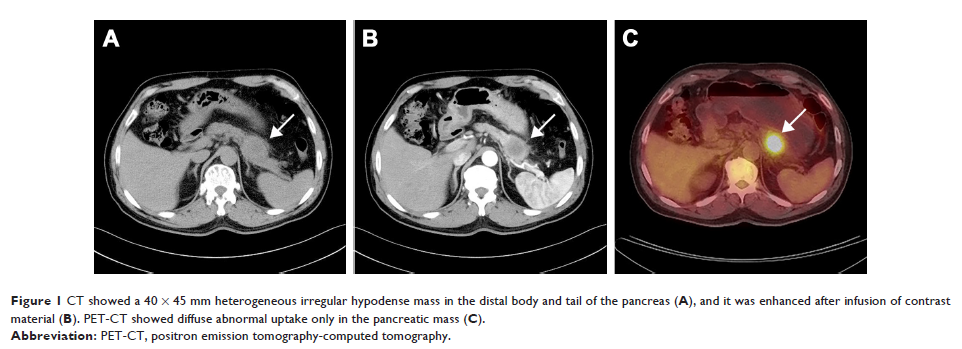

Case Report

- 作者:Pi-Jiang Sun, Yan-Hua Yu, Xi-Jun Cui

- 期刊:OncoTargets and Therapy